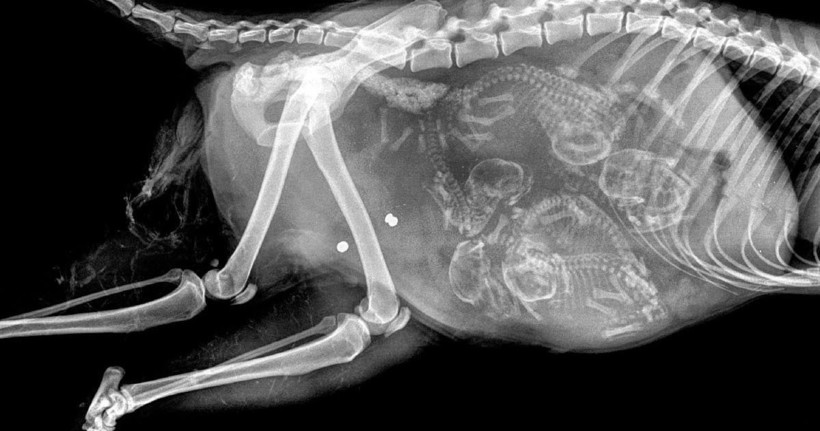

Собака и ее многочисленное будущее потомство